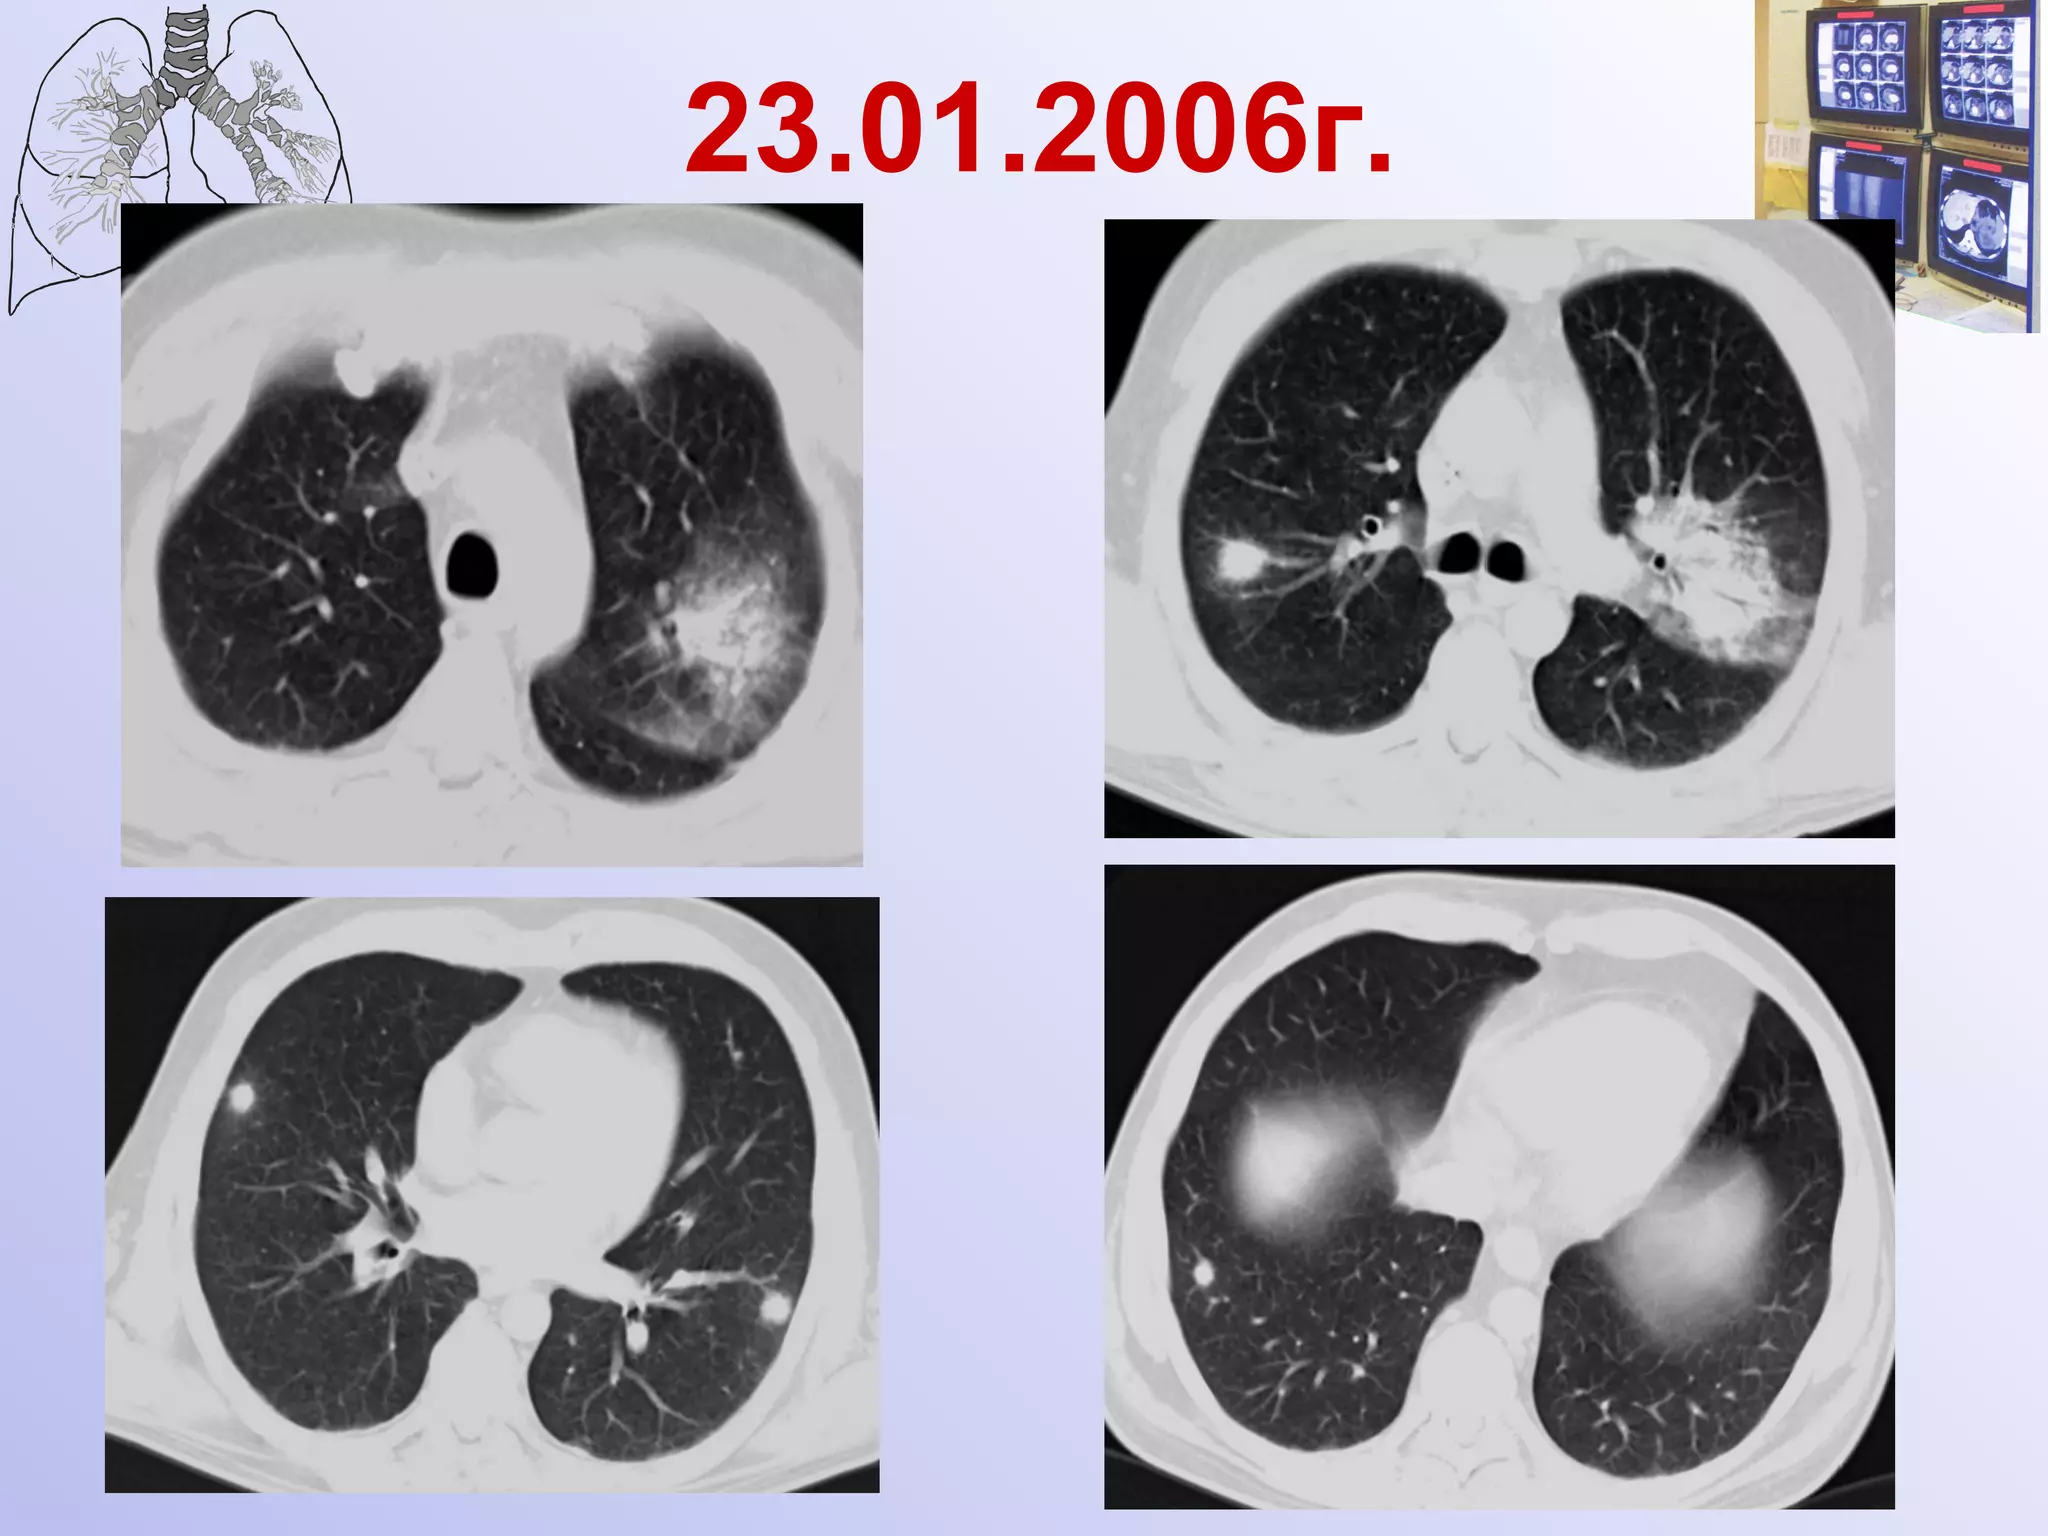

23.01.2006г.

Инвазивный микоз Развитие патологического процесса в легких за 4 дня Ершов

19.01.2006г. Малоинтенсивный очаг уплотнения в третьем межреберье справа